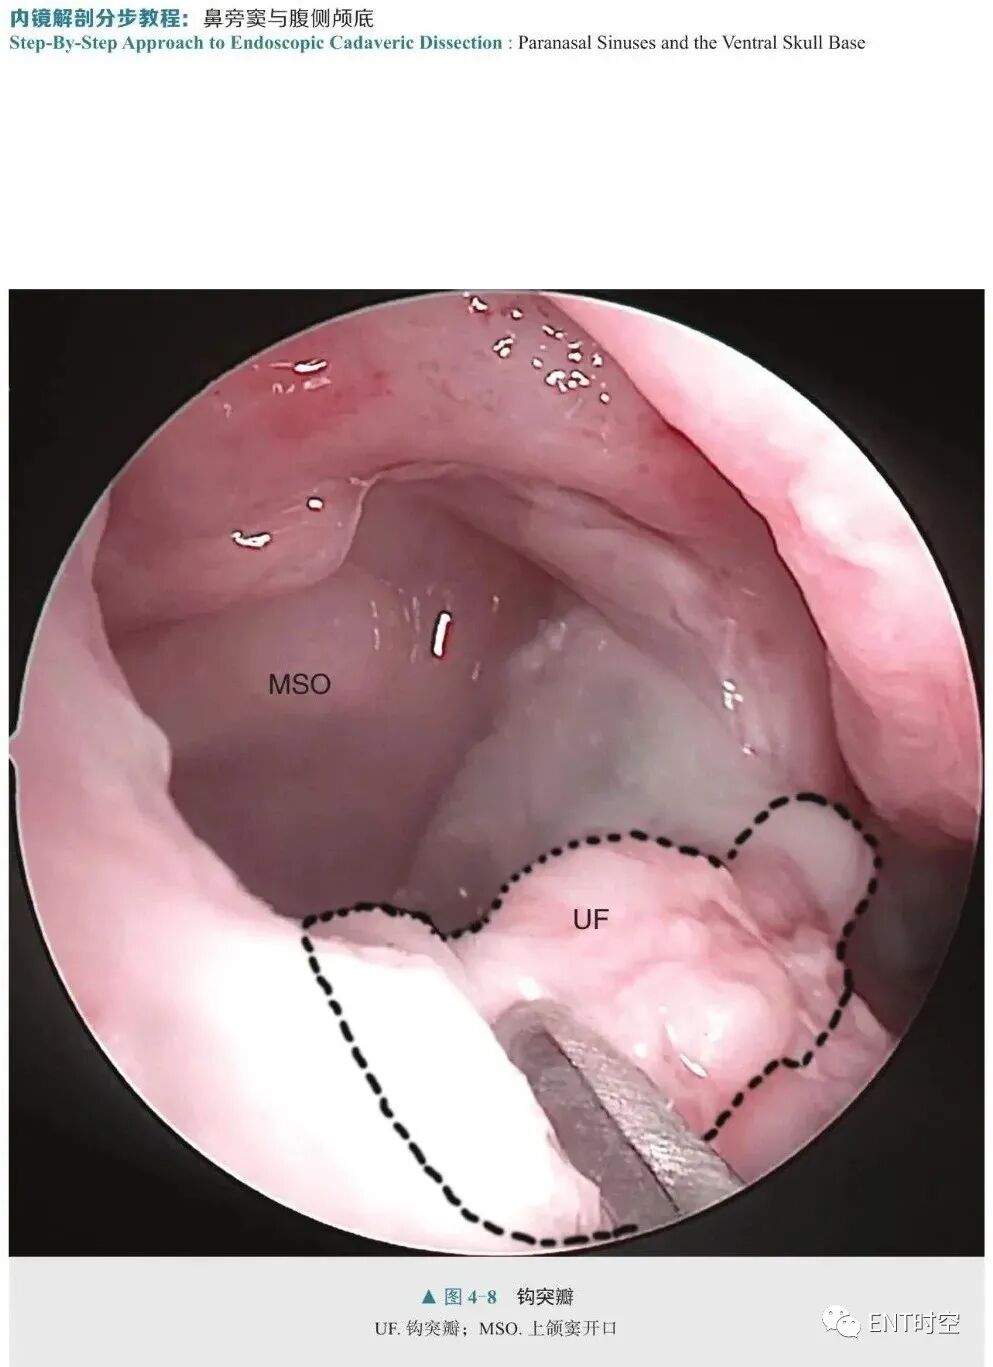

刘丕楠 主译《内镜解剖分步教程:鼻旁窦与腹侧颅底》是一部有关内镜下腹侧颅底解剖的实用操作教程。全书共8章,首先介绍了内镜的器械和基本操作过程,以及有关内镜手术的15条原则,之后开始介绍到达复杂颅底结构的各种入路,包括内镜入路到达鼻旁窦、腹侧颅底、脑神经及颅内间隙等。作者将内镜颅底外科整个手术通路的解剖结构做了层层递进式的描述,系统地展示了内镜下经鼻逐步暴露的各个重要环节,并通过精美生动的影像和图片全面展示了双人四手操作的精髓。本书内容新颖独特,图文并茂,适合有志从事神经内镜专科诊疗的医师、耳鼻咽喉科医师及神经外科医师阅读参考。

神经内镜是近20年发展起来的神经外科微创技术,是现代科学技术带给神经外科医生的一双“慧眼”,其以抵近观察和侧方视角的优势极大拓展了神经外科手术入路的选择。对于某些神经外科疾病,尤其是邻近或累及颅底腹侧面的病变,如颅咽管瘤、侵袭性垂体瘤、脊索瘤、脑脊液漏、翼腭窝肿瘤、颞下窝肿瘤等,神经内镜具有无可比拟的视野优势和解剖合理性。正因如此,近年来神经内镜手术在国内发展如火如荼,越来越多的神经外科医生希望掌握这项技术。鼻腔是内镜到达腹侧颅底的最主要手术通道,熟知、理解内镜视角下鼻腔、鼻旁窦及颅底腹侧解剖是开展内镜经鼻手术的必要前提。